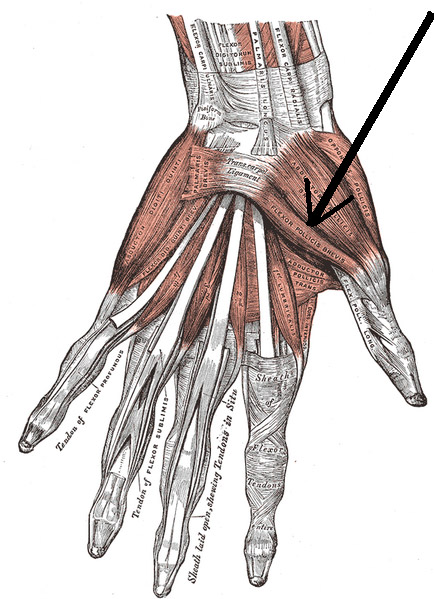

El músculo flexor corto del dedo pulgar forma parte de la eminencia tenar junto con otros tres músculos. Este grupo muscular se ubica en la base del dedo pulgar y se encargan de flexionar y mover el dedo pulgar hacia adentro, para realizar el movimiento de oposición del pulgar o pinza.

Se encuentra ubicado en posición medial e inferior al músculo abductor corto del pulgar y por encima del oponente del pulgar.

Consta de dos vientres musculares llamados superficial y profundo, que tienen orígenes diferentes en los huesos del carpo.

La porción superficial se origina en la saliente lateral del hueso trapecio. Algunas veces se encuentra un haz muscular que está anclado a la lámina fibrosa del retináculo de los flexores.

El origen de la porción profunda es en dos de los huesos del carpo. Alcanza la cara lateral del trapezoide y la cara medial del grande. Este vientre se encuentra íntimamente relacionado con el músculo flexor largo del pulgar.

Distalmente termina uniéndose con el fascículo superficial para formar un solo músculo que termina en el dedo pulgar.

Tanto la porción superficial como la profunda se convierten en una estructura tendinosa. Después de recorrer una parte del camino junto al flexor largo del pulgar, el fascículo profundo termina uniéndose al superficial.

Formando un tendón único, el flexor corto del pulgar se inserta en la base de la falange proximal del pulgar y en el hueso sesamoideo que se encuentra inmerso en los ligamentos que forman parte de esa articulación.